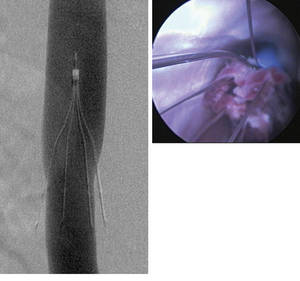

Images of an IVC filter obtained 2 months after implantation: Left, Cavogram demonstrates mild IVC narrowing but does not show filling defects within the filter; Right, Angioscopic image from below shows debris within the filter..